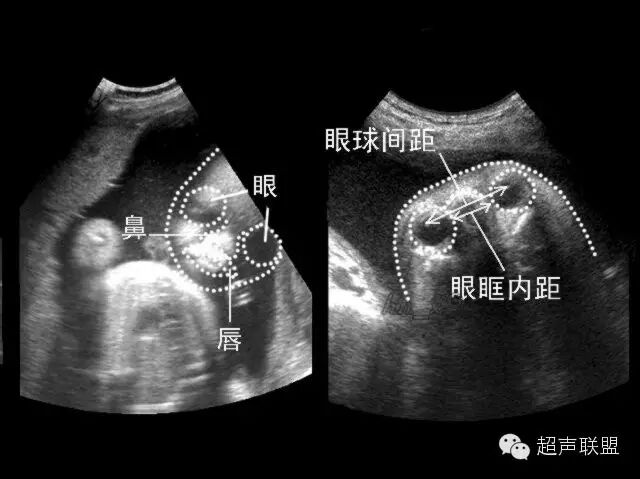

(一)双眼球水平横切面

1.扫查方法:声束平面通过双侧眼球,横切胎儿头部即可获得,声束尽可能从前面进入并与双侧眼球中部边线垂直。这是进行胎儿颜面部横断扫查的基准切面。

2.判断标准:要求在同一平面内显示双侧晶体及眼球图像,且双侧晶体及眼球大小基本相等。此外,该切面还可显示眼眶骨性高回声、鼻根部骨性高回声及颅内结构。

3.主要观察的解剖结构及内容:

(1)眼球:双侧眼球及眼球内晶体大小基本相等,晶体内部为无回声。

(2)眼眶的大小、 眼内距及眼外距:眼眶的大小又称眼距是指眼眶的左、 右径;眼内距是指双侧眼眶内侧壁的距离;眼外距是指双侧眼眶外侧壁的距离。20周以上胎儿正常时眼内距约等于眼距。

(3)鼻根部骨性结构:呈三角形,前上端窄小,由一对鼻骨板构成,下端宽大,由位于两侧上颌骨额突构成。双侧鼻骨在中线汇合。

4.临床意义:双眼球横切面是颜面部系列横切面的基准切面,尤其在显示上唇及上腭时,双眼球横切面是一个非常重要的参照平面,对准确判断是否存在唇腭裂有非常重要的意义。该切面可明确诊断一侧或两侧小眼畸形、无眼畸形、独眼畸形、先天性白内障、眼距过近、眼距过远。对鼻骨发育不良、缺失、鼻发育不良等有辅助诊断价值。